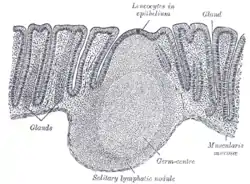

Section of mucous membrane of human rectum. X 60. Layers of stomach wall

Layers of stomach wall General structure of the gut wall showing the Muscularis mucosa.

General structure of the gut wall showing the Muscularis mucosa.